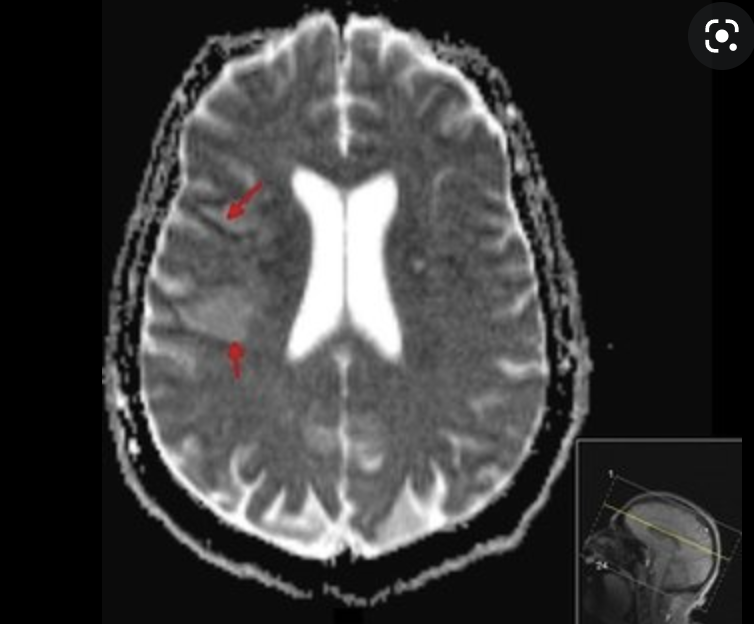

meningitis, vasculitis, stroke,

brain abscess